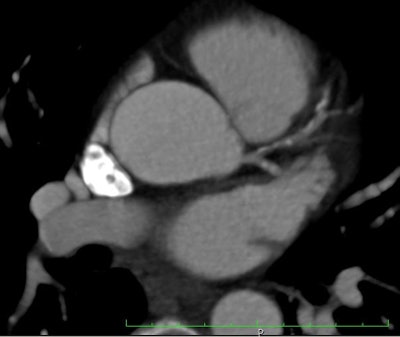

| A contrast-enhanced acquisition was performed after oral beta-blockade at a heart rate of 59 bpm (range, 57-61 bpm) (dual-source scanner with bolus tracking in the ascending aorta at 100 HU, prospective ECG triggering at 100 kVp, b26f soft-kernel reconstruction). This scan was suboptimal due to motion, misregistration, and beam hardening in the proximal left anterior descending (LAD) artery (image above). Additionally, the staff, nervous about scanning a colleague, had forgotten to give the sublingual nitrate. Images were reviewed as they came off the scanner by the radiology fellow and supervising cardiologist. The patient gave permission to repeat the scan to improve diagnostic confidence, due to the calcified LAD lesion. |